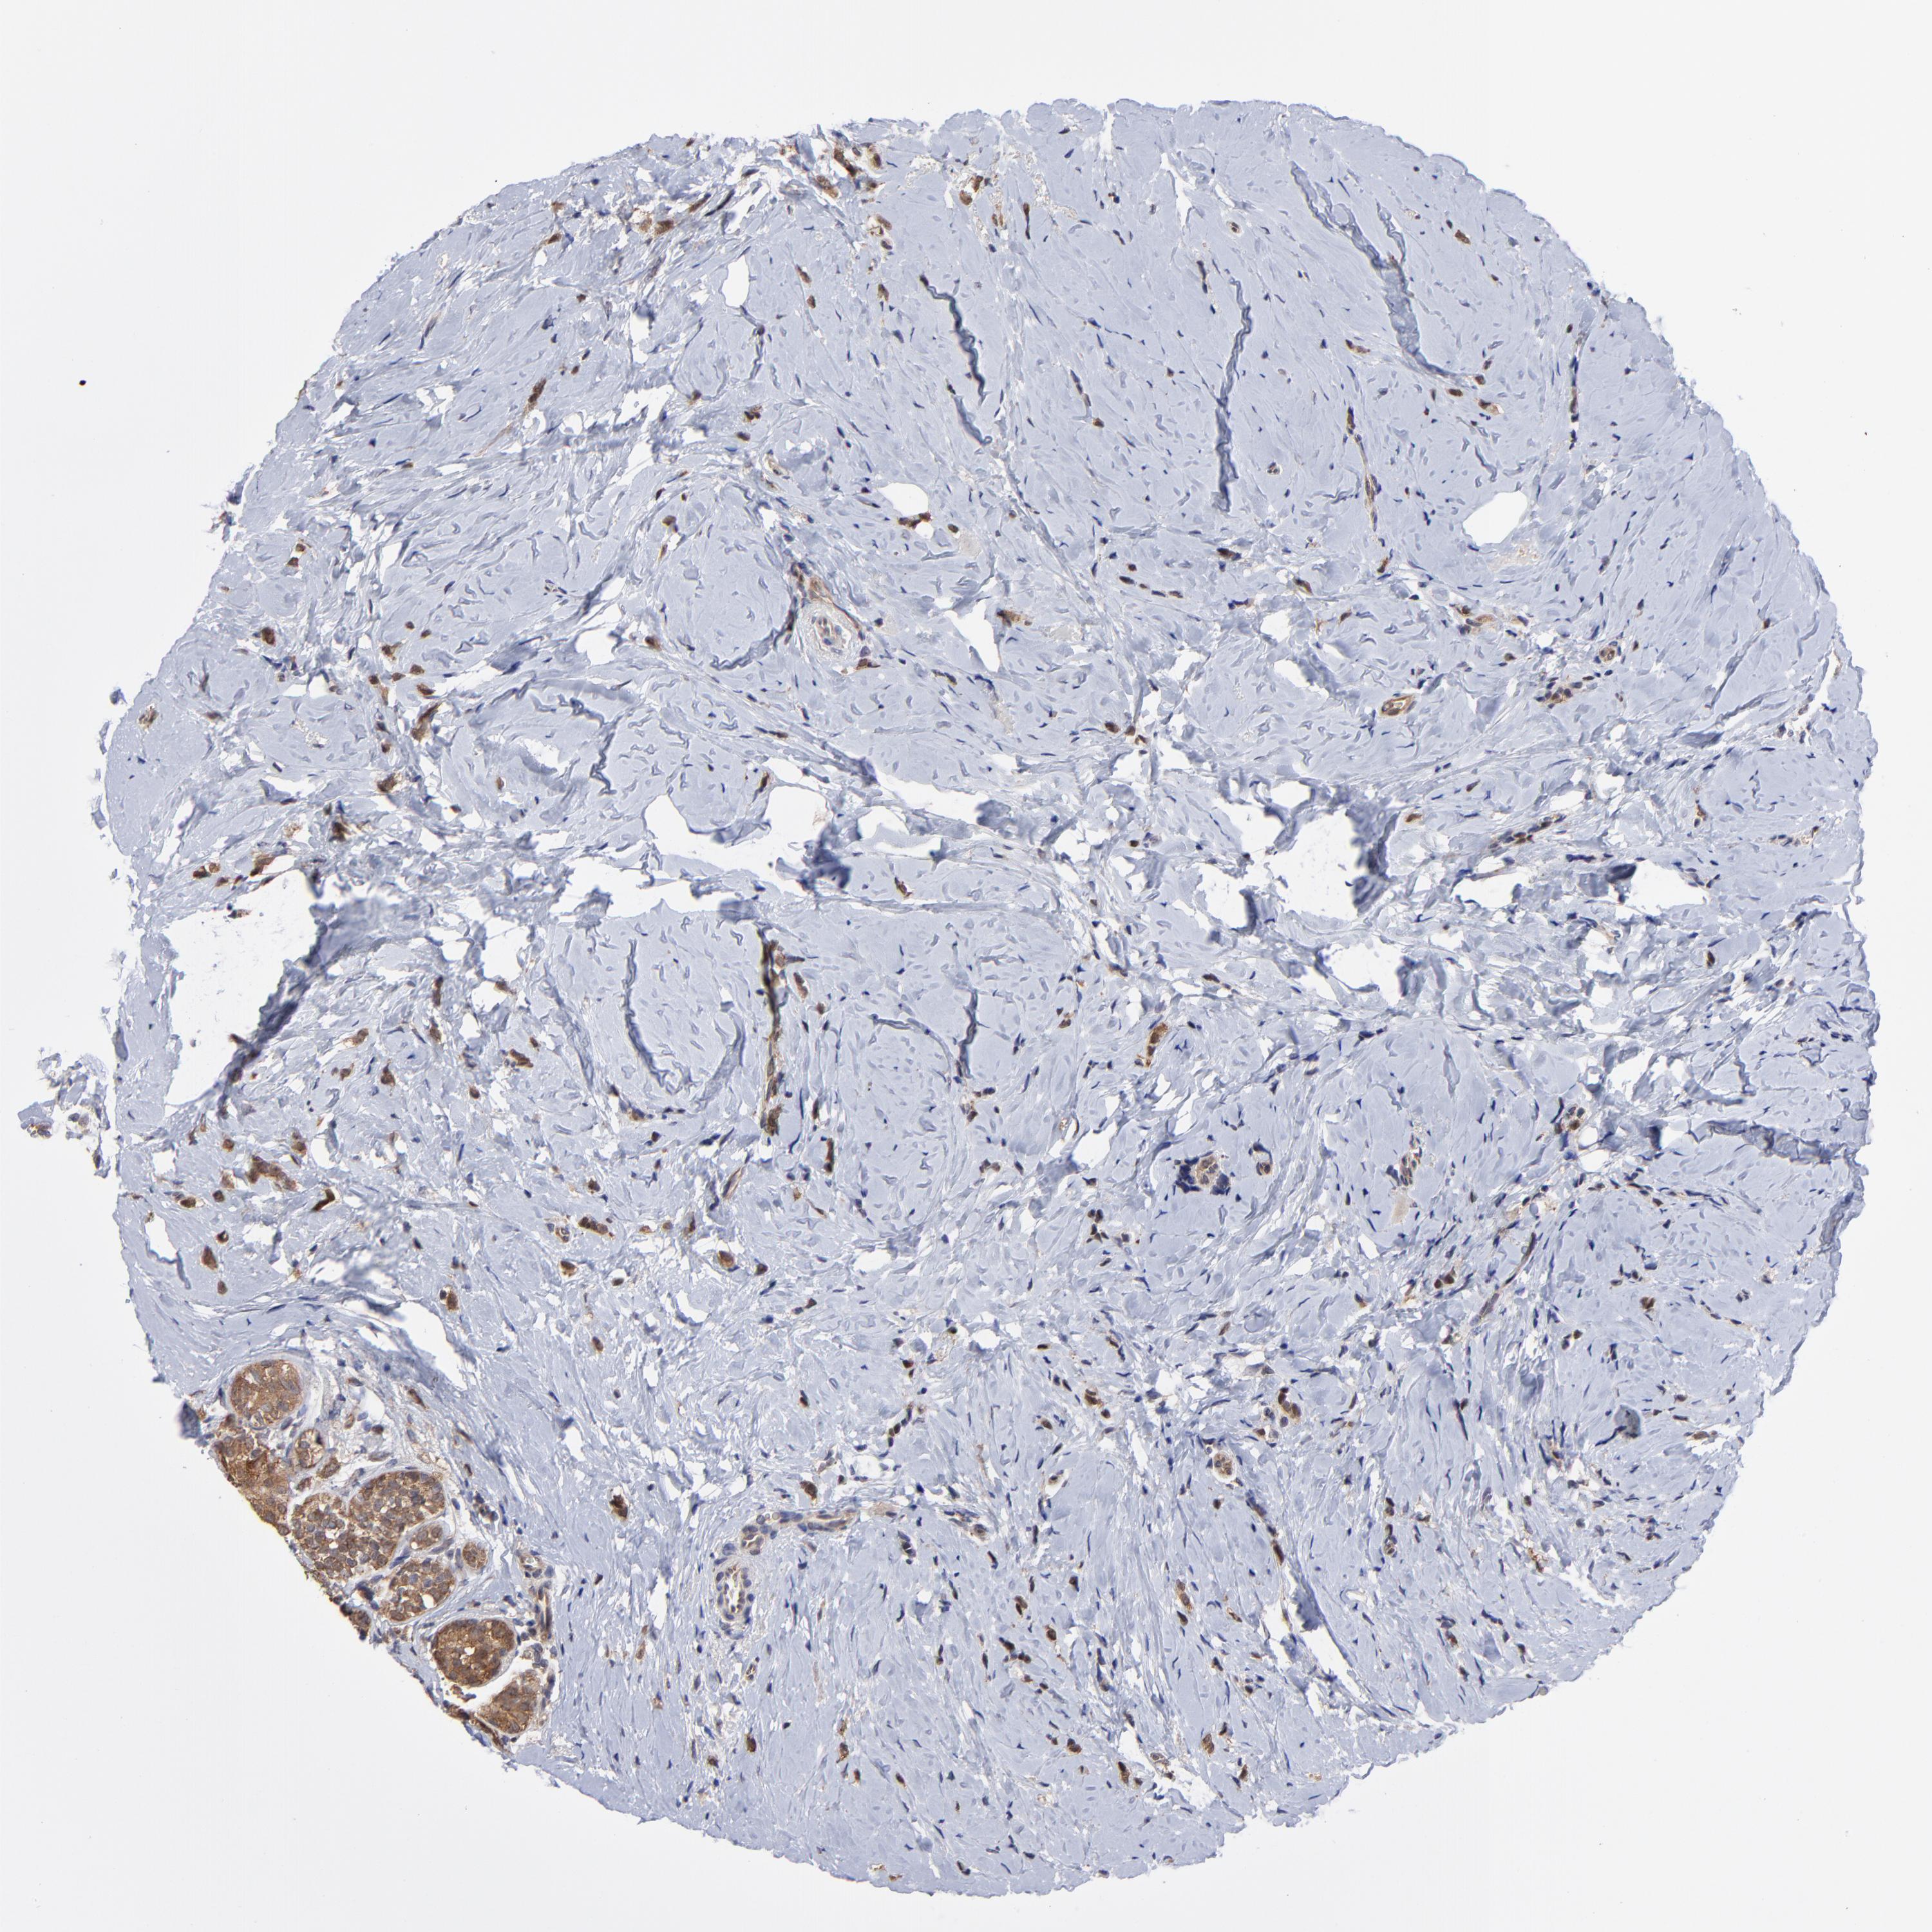

CANCER BREAST CANCER Show tissue menu

BRCA TCGA BRCA VALIDATION PROTEIN EXPRESSION

ANTIBODIES

AND

VALIDATION